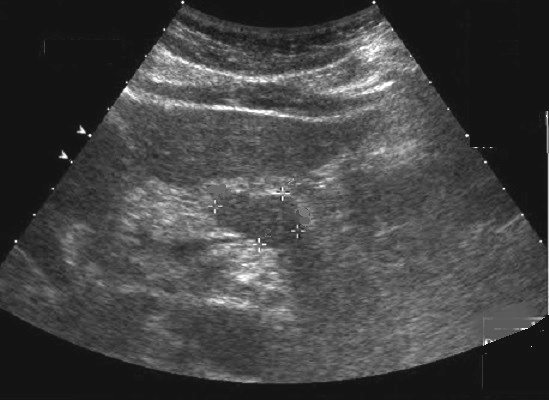

Echographie :

Est technique de choix de premiere de l'intention

dans des cas avait de douleur abdominale en plus avec une

bilan d'ictere de la maladie ce qui en suspecte d'une

adenocarcinoma du pancreas . Image

echo graphique direct du tumeur est image

lesionaire de masse hyperechogene a bord flou non de

contour de la glande . Technique echographique est moindre

de recherche dans les cas de petite tumeur a inferieure de

2mm et sa sensibilite de recherche varie de 55-90% des cas .